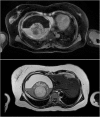

Presentation of case: We present a case of a 65 year-old female who presented to hospital with sudden onset abdominal pain from a centrally located ruptured hepatic teratoma on CT scan. The patient underwent urgent surgery. The diagnosis of cystic mature teratoma was confirmed on histopathology. Patient was discharged on post-operative day 5. At 12 week follow-up, no post-operative complications were identified.

Discussion: Hepatic teratomas are a rarely encountered neoplasm, especially in the adult population. Our case report is unique, as it represents the only clinical presentation of mass rupture in an adult liver teratoma. CT scan identified a well circumscribed mass containing adipose tissue, fluid, and calcifications characteristic of teratoma. Complete surgical resection is mainstay treatment. A definitive diagnosis of a mature teratoma is confirmed by histopathological findings.